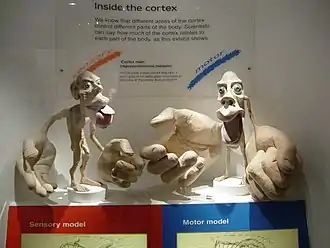

In the process of treating epilepsy, Wilder Penfield produced maps of the location of various functions (motor, sensory, memory, vision) in the brain.[43][44] He summarized his findings in a 1950 book called The Cerebral Cortex of Man.[45] Wilder Penfield and his co-investigators Edwin Boldrey and Theodore Rasmussen are considered to be the originators of the cortical homunculus.[46]